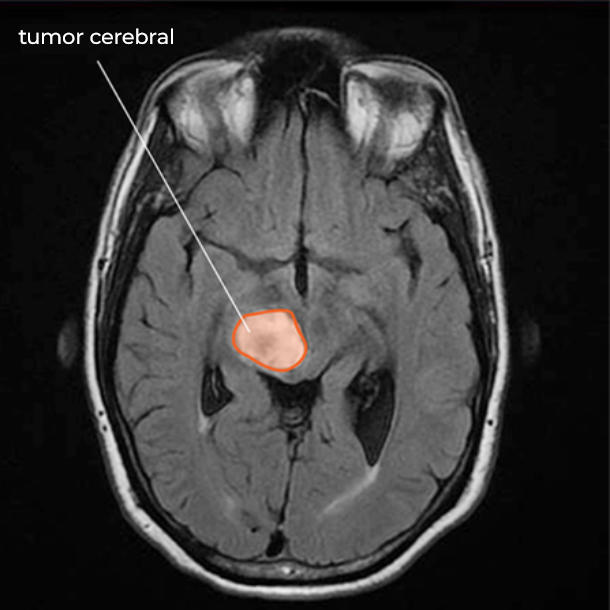

Un nuevo estudio halló que una prueba de sangre, denominada biopsia líquida, puede revelar si un niño con un tipo de tumor cerebral conocido como glioma difuso de línea media tiene una mutación genética específica asociada con dicha enfermedad.

Los investigadores se enfocaron en una mutación genética denominada K27M, que ocurre en el gen H3 y está asociada con una forma maligna de la enfermedad. La prueba identificó la mutación en sangre o en líquido cefalorraquídeo (o en ambos) en 42 de los 48 pacientes del estudio con gliomas difusos de línea media que se sabía eran portadores de la mutación.

Al presente, no hay tratamientos eficaces para estos tumores cerebrales poco comunes, y la mediana de supervivencia para los pacientes es menos de un año.

Al comparar las exploraciones por RM y los resultados de biopsias líquidas de 12 pacientes con un tipo de glioma difuso de línea media, denominado glioma pontino intrínseco difuso (DIPG), antes y después de recibir radioterapia, los investigadores hallaron que los resultados de la biopsia líquida correspondían a cambios en los tumores cerebrales.